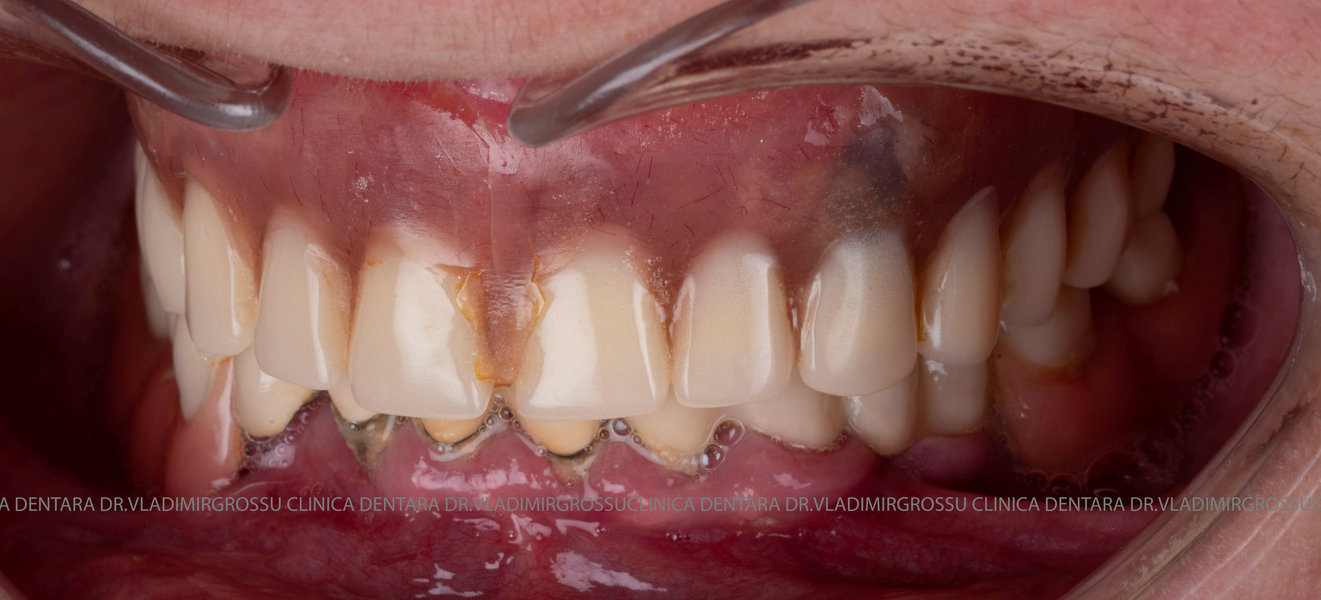

Această metodă este recomandată pacienților edentați total sau celor cu lipsuri dentare multiple. Procedura se realizează într-o singură etapă, iar pacientul primește proteza provizorie în ziua următoare intervenției. De regulă, proteza provizorie este realizată din masă plastică frezată. Suturile se îndepărtează după 5-7 zile.

Etapa provizorie:

- 4 implanturi;

- 2 multiunit-uri drepte și 2 multiunit-uri angulate, conform necesităților protetice;

- 4 abutment-uri provizorii pe multiunit-uri;

- Proteză provizorie din masă plastică frezată sau proteză mobilizabilă pregătită și ajustată la componentele protetice.